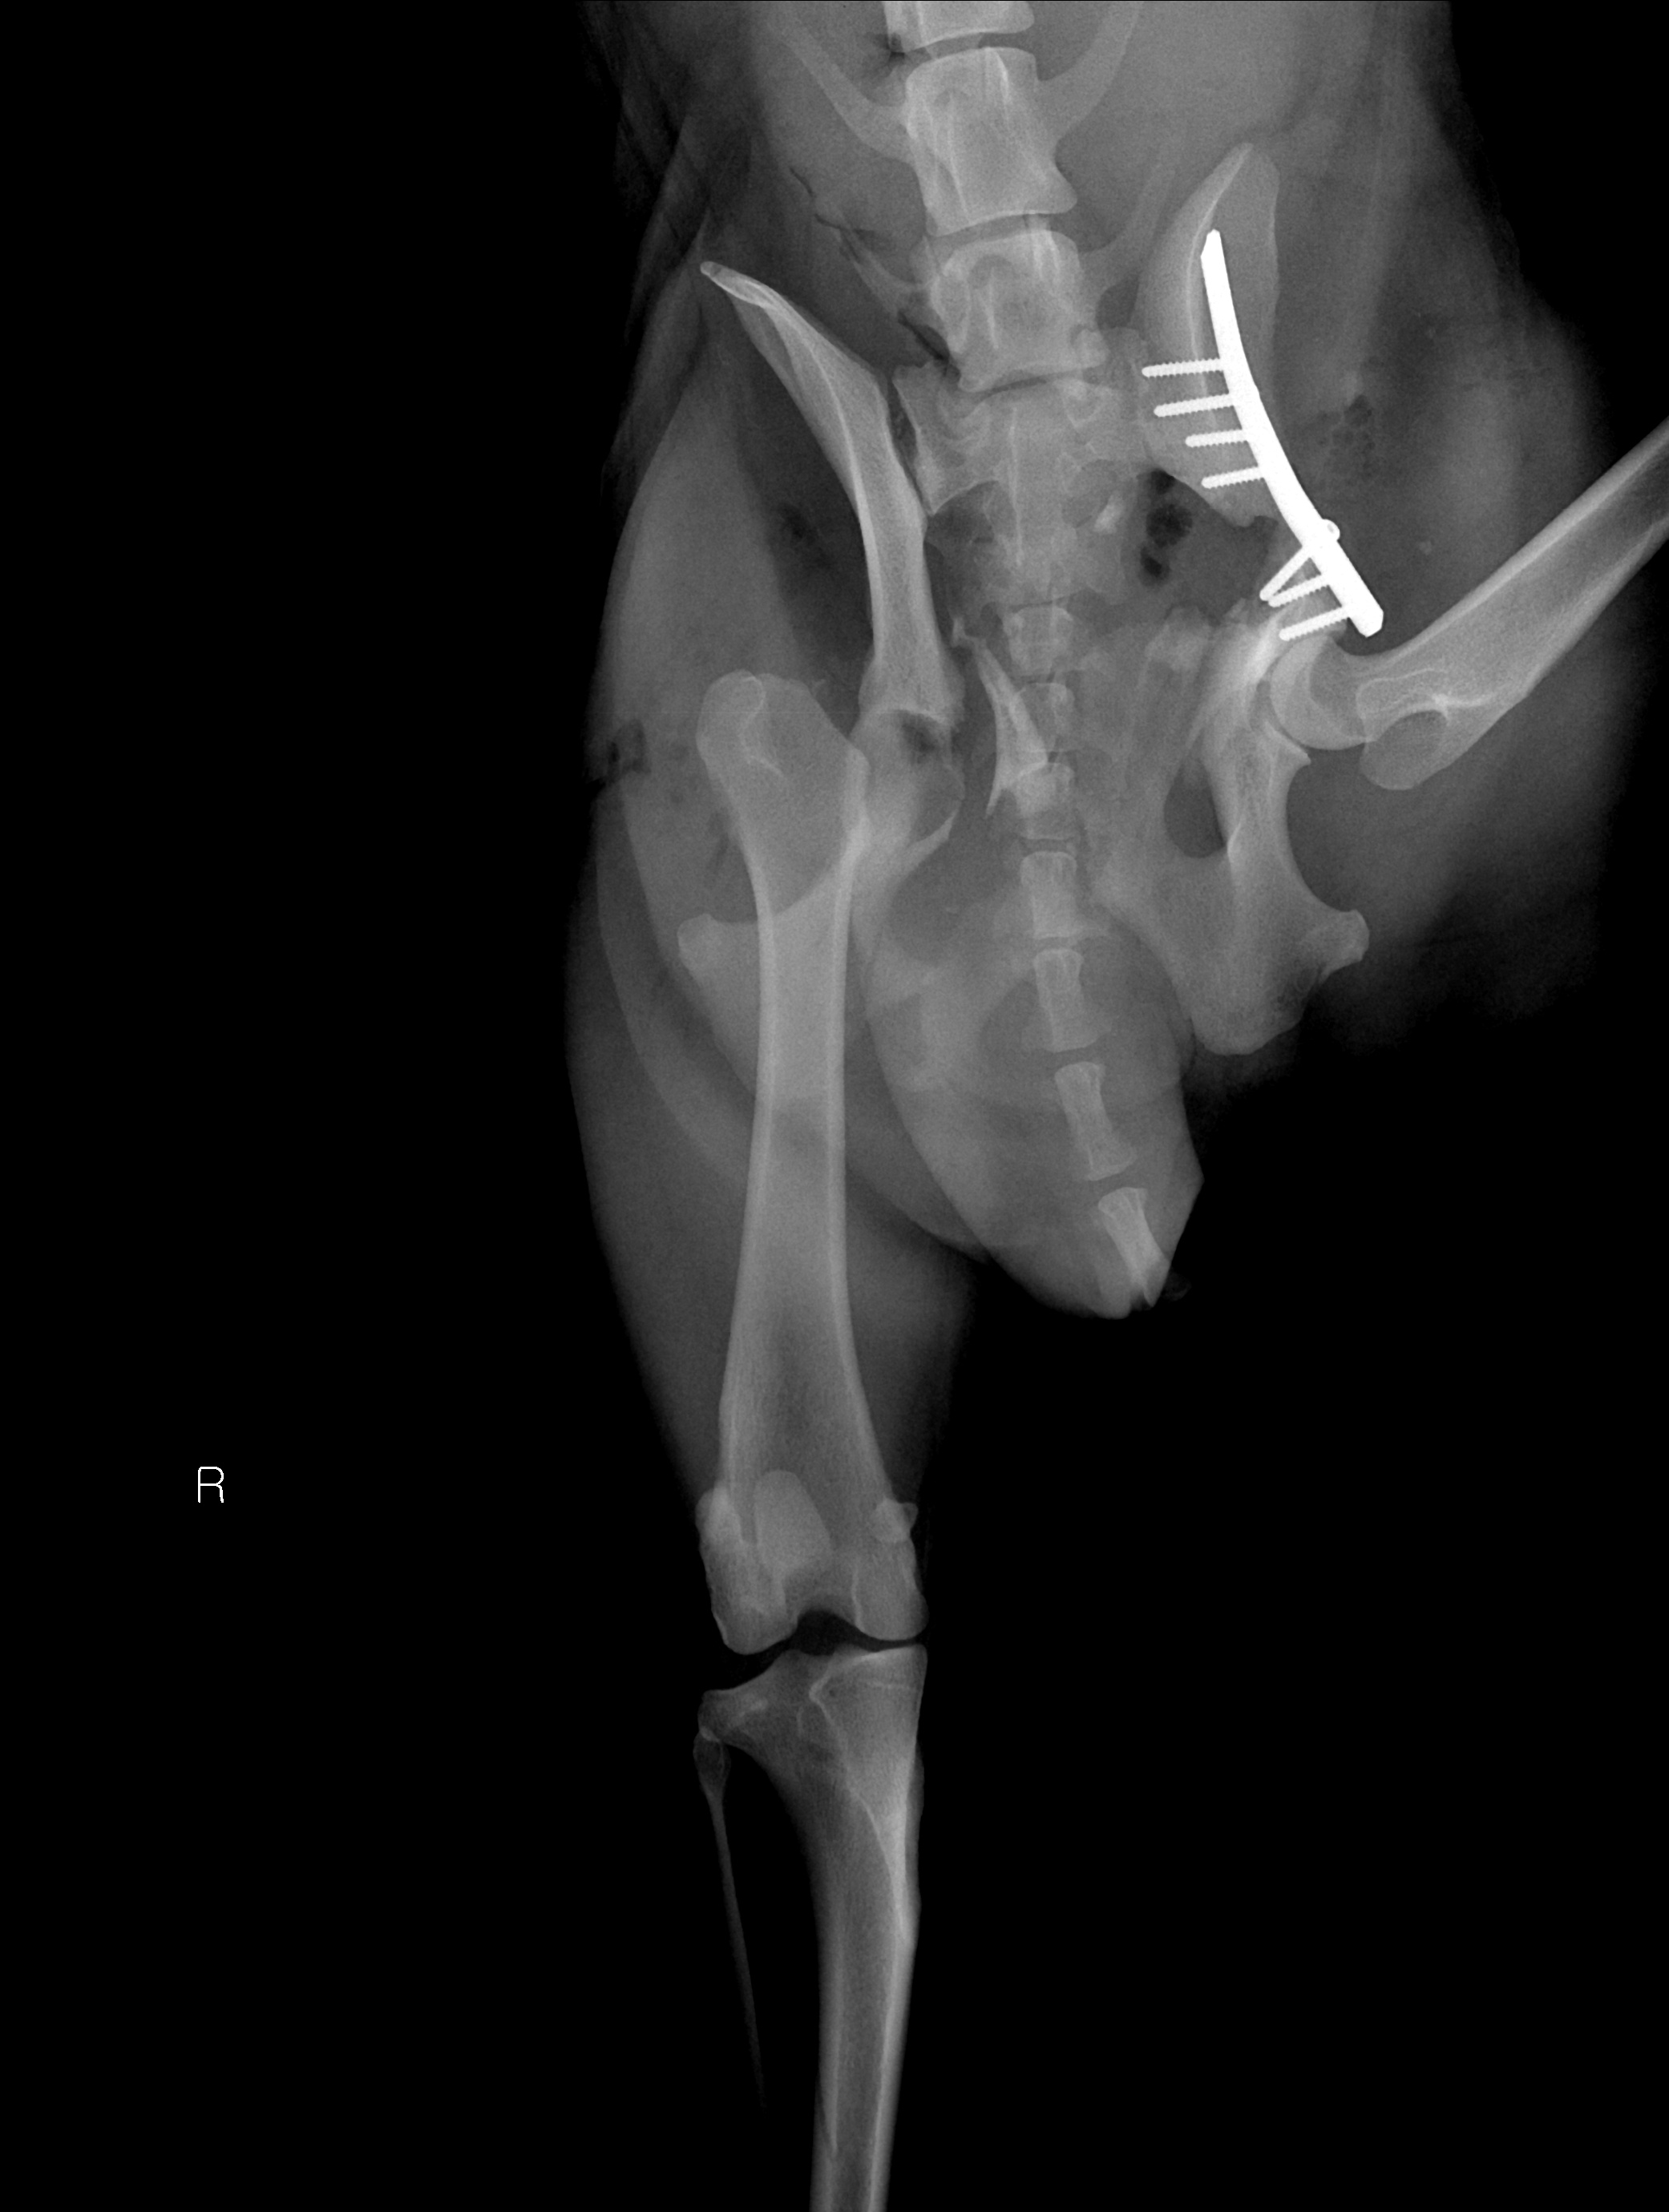

엑스레이 검사에서 흉복부에는 특이 소견이 없었고, 좌측 골반골절과 우측 고관절 탈구가 확인이 되었습니다.

1차 수술에서는 좌측 골반 골절부의 대한 골절 수술이 진행이 되었고, 골절부 골편이 여러 개로 나누어져 있어 섬세한 수술 스킬이 필요한 상태였습니다.

플레이트를 이용해 여러 개로 나누어진 뼈들을 맞춰 1차 수술이 마무리되었습니다.

오른쪽 탈구된 고관절은 대퇴골두에 의해 통증 유발과 함께 관절 운동을 저해하고 있어 탈구부 대퇴골두를 절단해 주어 수술을 마무리해 주었습니다.